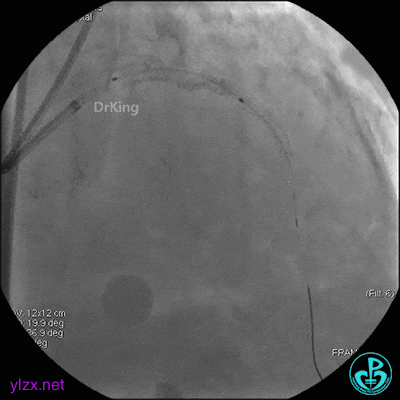

EBU指引导管到位,导丝通过闭塞段到达前降支远端,经指引导管冠脉内推注替罗非班6ml,前降支恢复3级血流,闭塞段局部残余狭窄严重,2.0×15mm球囊扩张前降支近端闭塞处后再次冠脉内推注替罗非班8ml。下台继续治疗。

1周后复查造影,见粗大前降支3级血流,近端严重狭窄伴管壁严重钙化影,病变累及前降支开口。

球囊扩张后前降支中段植入支架。